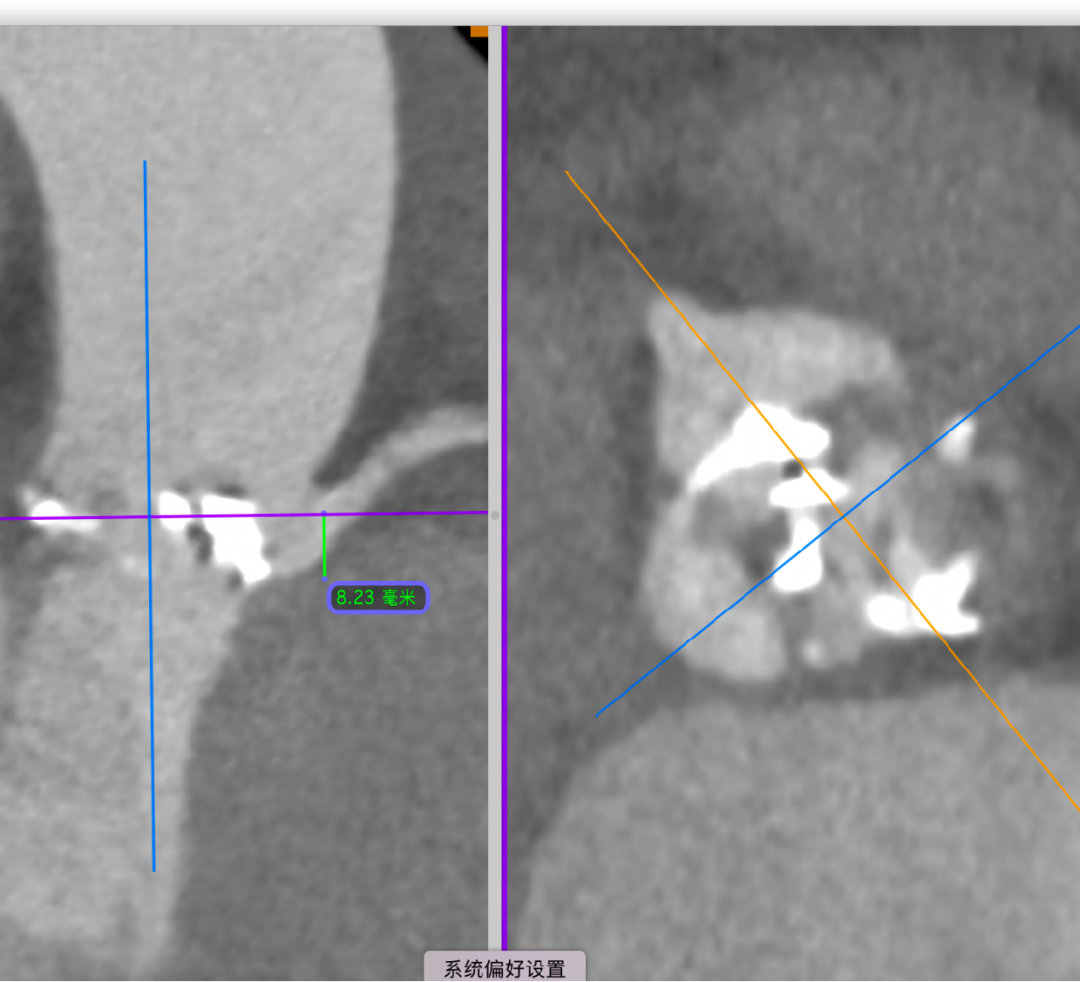

主动脉根部CT断层

根部角度/瓣环/左室流出道

瓣上结构2,4,6,8,10,12mm

左冠风险评估